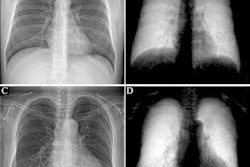

Lateral conventional attenuation (a, b, e, f) and co-registered dark-field (c, d, g, h) images of two spine specimens. Vertical (a, c, e, g) and horizontal (b, d, f, h) scans of the spine specimen of a 77-year-old female with osteoporosis (bone mineral density = 65.75 mg/dL) (a–d) and a non-osteoporotic spine specimen (e–h) of a 61-year-old female (bone mineral density = 169.38 mg/dL).Image available for republishing under Creative Commons license (CC BY 4.0 DEED, Attribution 4.0 International) and courtesy of European Radiology Experimental.